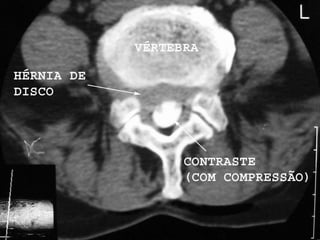

• É frequentemente realizada imediatamente após a

conclusão da mielografia enquanto o material de contraste

ainda está presente dentro do canal espinhal. Esta

combinação de estudos de imagem é conhecido como

mielotomografia.

• As relações anatômicas são mais bem visualizadas

quando os cortes de TC axiais são feitos

perpendicularmente ao eixo central do canal espinhal. O

uso de reconstrução computadorizada de imagem

consequente aos cortes tomográficos em planos frontais

ou sagitais dão orientação e resolução espacial.

• Esse exame irá acrescentar mais 15 a 30 minutos ao

tempo total do exame.